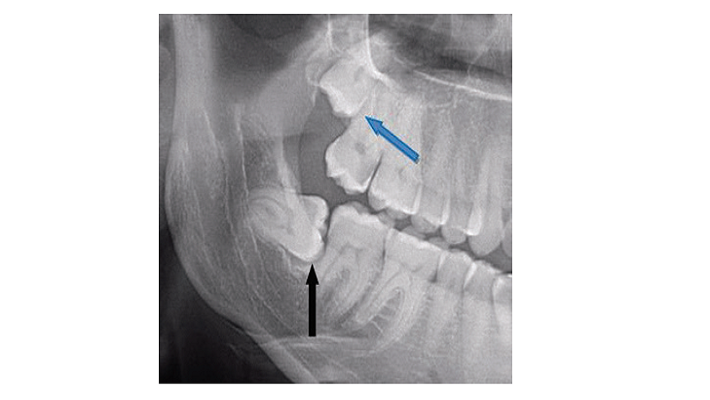

בתמונה: שן בינה תחתונה הנמצאת במגע הדוק עם השן הסמוכה לה והשן העליונה כלואה בעמדה גבוהה בלסת